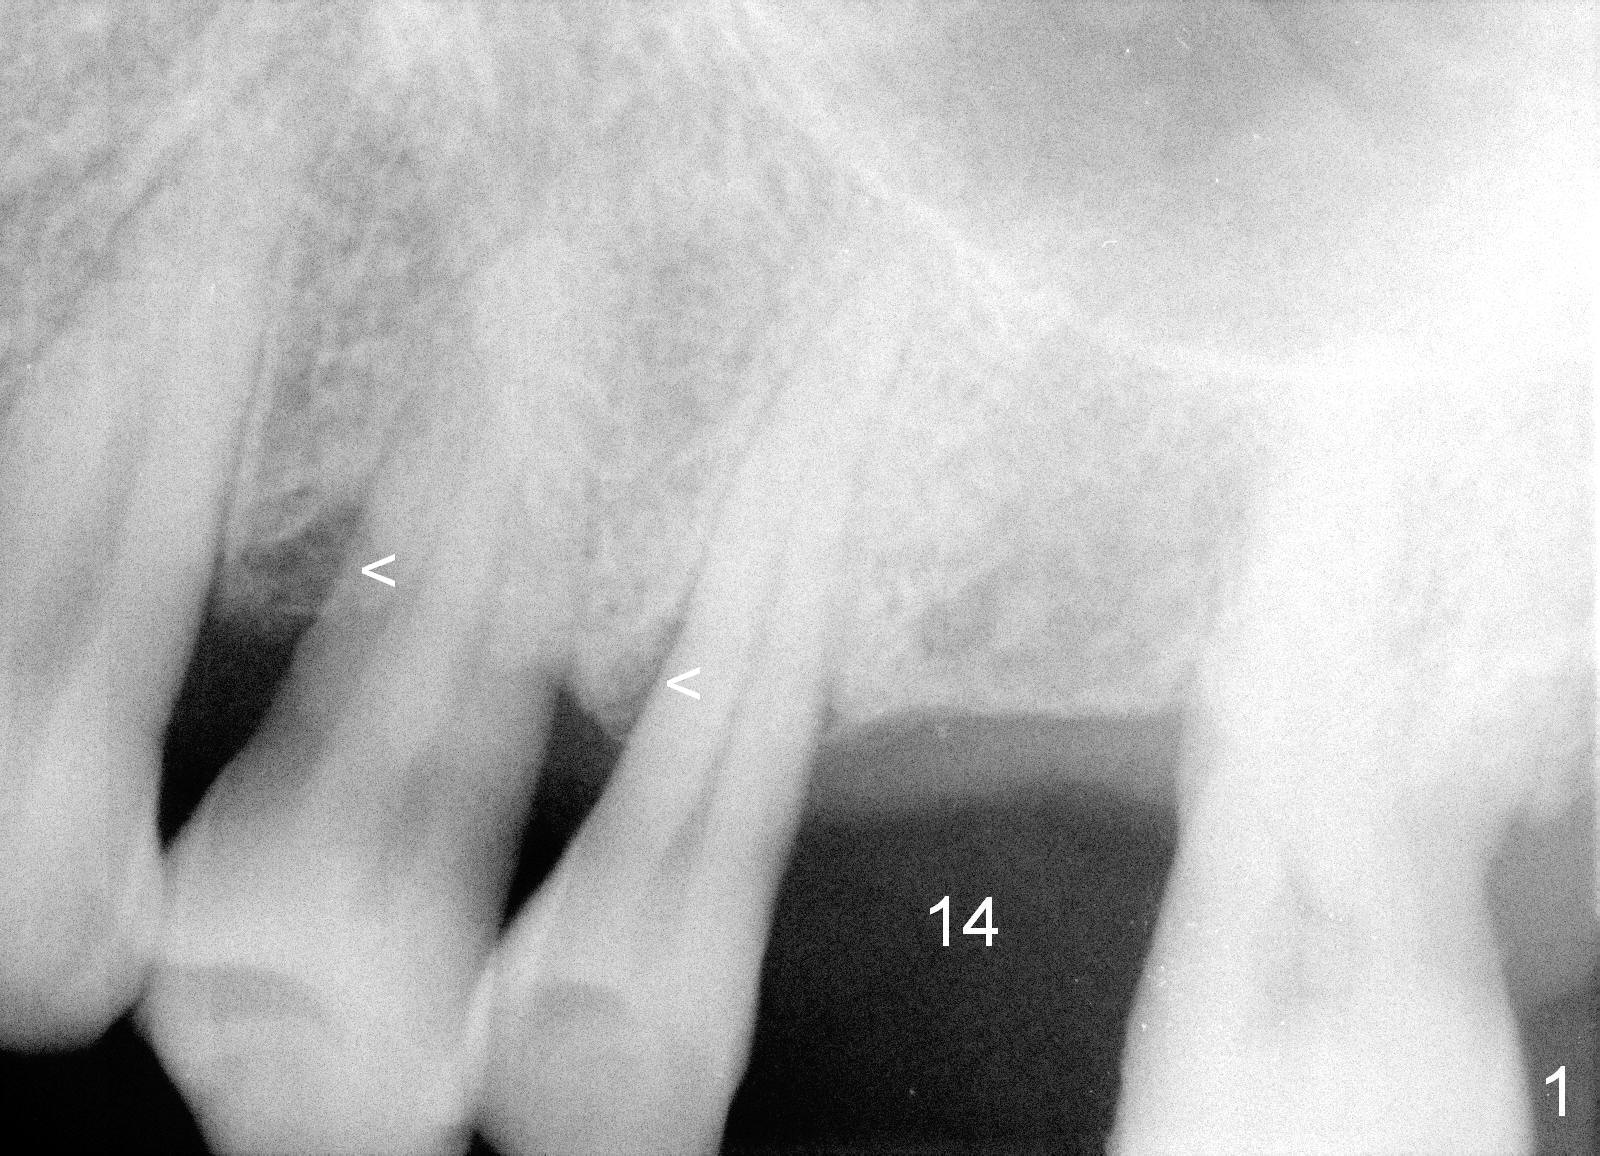

A 58-year-old man has multiple missing teeth including #14; the remaining teeth has sign of occlusal trauma (bone loss, Fig.1 arrowheads). The mesiodistal space of #14 is 8 mm (Fig.2). It appears that a 4.5x14 mm implant is appropriate for the site with sinus lift. Scalpel will be used to initiate osteotomy and bone expansion in case the bone density turns out to be low. To prevent the sinus membrane perforation, use a shorter implant (11 mm, Fig.3).